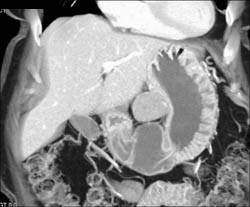

2 Cm GIST Tumor